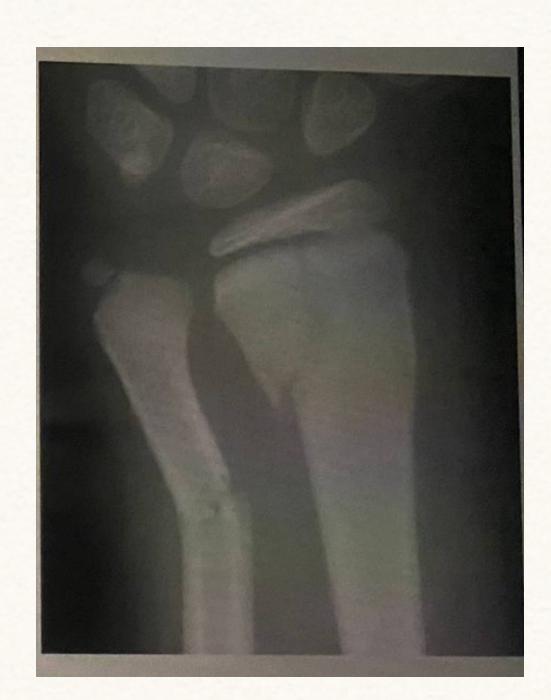

Case: A man involved in a road traffic accident (RTA) where a car ran over his forearm. X-ray showed fracture of the forearm.

Diagnosis?

- Compartment syndrome

What are the clinical features?

- The 5 Pโs:

- Pallor

- Paresthesia

- Pain (out of proportion to injury)

- Paralysis

- Pulselessness

Management?

- ABCโs (Airway, Breathing, Circulation)

- Correct hypotension

- Remove circumferential bandages & cast

- Position limb at level of the heart

- Supplemental oxygen

- Fasciotomy (definitive treatment)